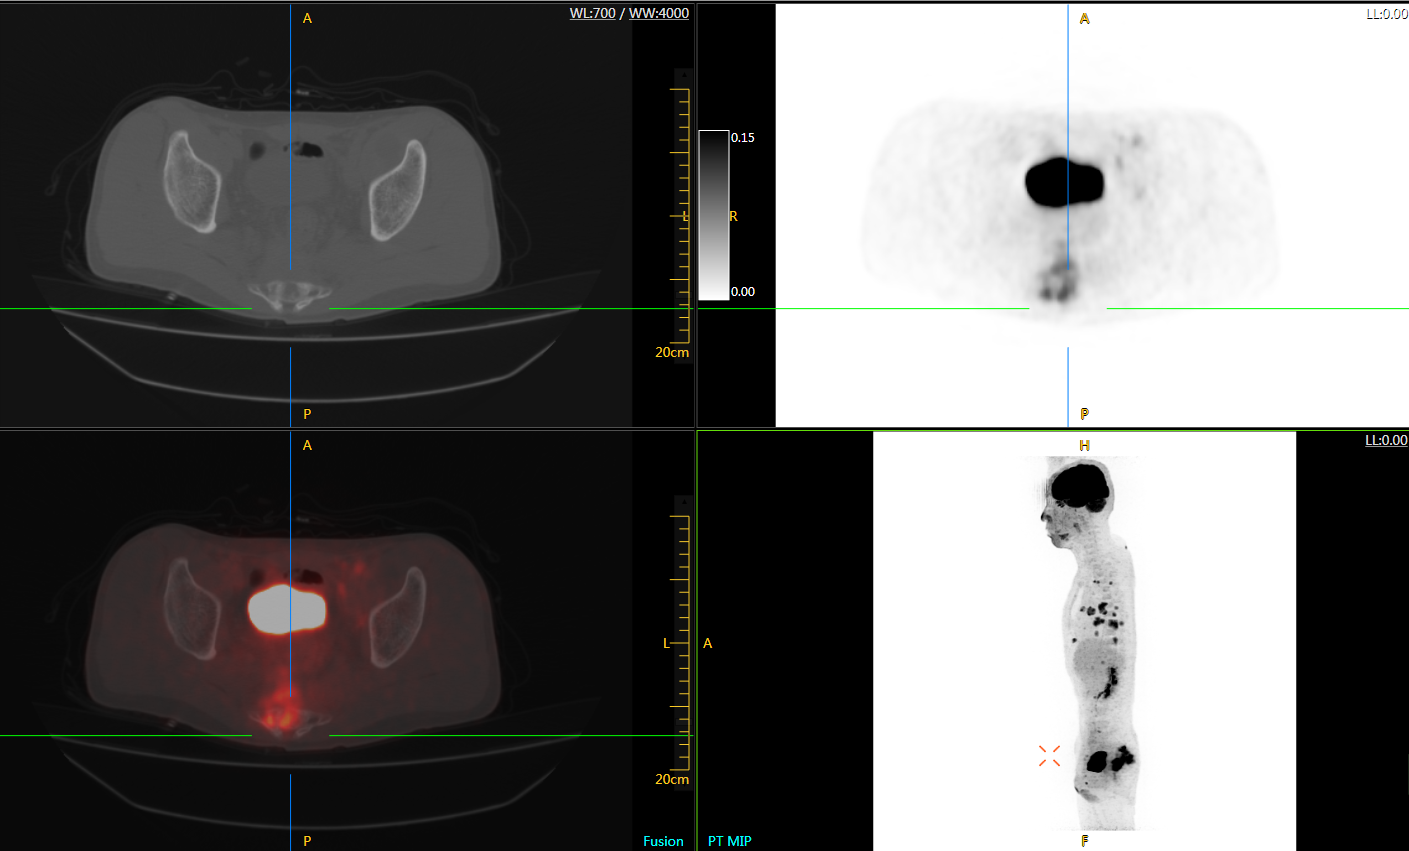

直腸癌

男,45歲,直腸癌術(shù)后9個月,發(fā)現(xiàn)肺占位

臨床診斷:直腸區(qū)術(shù)后改變,復(fù)發(fā)伴骶骨受累,雙肺多發(fā)轉(zhuǎn)移